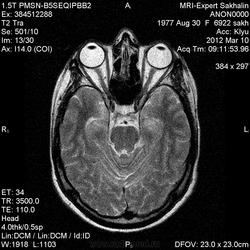

Направительный диагноз:головная боль напряжения.

Краткий анамнез заболевания, жалобы: головные боли,снижение памяти, раздражительность, снижение аппетита в течение 3-х месяцев.

Подозреваю демиелинизацию,гиппокампальный склерз ( тогда базальные ядра и ножки при чем?),ишемические проявления -не знаю!Помогите , пожалуйста, начинающему доктору!

Лимбический энцефалит? Паранеопластический процесс? А где диффузионные программы- не помешают. Нужно подумать (или спросить у ннемо, например))).

Написала дифф.ряд: лимбический энцефалит, лимфому ЦНС, герпетический энцефалит.

С лимфомой верифицированной не встречался, картина не противоречит паранеопластическому или герпетическому энцефалиту. Склероз гиппокампов: нет уменьшения их размеров, зоны изменений сигналов гиппокампами не ограничиваются, есть кроме височных долей и в ножках мозга, опять же накопление контраста.

Женщина 1977 года рождения.Со слов мужа , около 3/х мес. назад начались головные боли, снижение памяти, раздражительность снижение аппетита.Перенесла какую-то инфекцию типа ОРЗ.С ней разговаривать трудно-мало что помнит.На асоциальную , наркоманку не похожа-приличная с виду женщина.Неврологический статус хотела выяснить у лечащего врача по телефону, но она живет в районе,и телефон не указала .Визуально-неврологический статус без особенностей.В направлении-головная боль напряжения .Нет указаний -на что обратить внимание.

Еще гайморит тут правосторонний, может это несколько качнет весы в сторону воспалительного процесса?

Ишемические изменения и темпоральный склероз - нет.

Есть и давно подтвержденное понятие паранеопластический лимбический энцефалит - как вариант примерно так и будет выглядеть.

В данном случае больше данных за воспалительный энцефалит - есть синусит (не нравиться гиперинтенсивное включение парацентрально в пазухе -грибок????) .

С учетом накопления контраста да и по локализации однозначно не опухоль, не инсульт, не травма. Из классики да действительно герпес любит виски, также и иные вирусные могут быть (этиологию иной раз не угадаешь - бессмыслено), может быть и тбс. но сос четов не сбрасывал бы паранеопластический - тем более женщина да и контраст накопила как бы не молочка?? Ну и совсем чтоб запутать нет ли В20? только на внешний вид и на мужа не надо ориентироваться - у нас и у врачей и у студентов мед вузов бывает - пройденный этап(((

Была у нас пациентка (картинки предоставить не могу , так как поезд ушел) , картина была один в один , только в меньшей степени выраженности. Тоже возникло после перенесенной ОРВИ, после лечения приходила на контроль - мр- сигнал вернулся к норме. Так что согласна с энцефалитом. При паранеопластическом процессе все же более четкие границы , я так думаю. и распостраненность несколько другая..